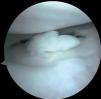

Figura 4 Artroscòpia. Lesió condral àmplia en ròtula, faceta externa i cresta condral.

Es practica una artroscòpia, en la qual s'observen (figs. 2, 4, 6-8):

• Múltiples fragments condrals lliures de vores agudes, que s'identifiquen com recents, i de vores rodones que es cataloguen com antics.

• Lesió condral anfractuosa extensa, amb fragments inestables en cres-ta de la ròtula i en faceta externa, de grau III.

• Resta d'estructures intraarticulars íntegres.

• Es procedeix a l'exèresi dels cossos lliures i la regularització de la lesió condral seguida d'estabilització per vaporització.